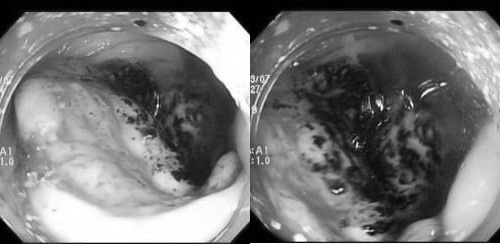

Hình ảnh ung thư đại trực tràng ở một người trẻ. Ảnh: BVCC.

Trường hợp chị P.V.P.U. (35 tuổi) đến khám chỉ vì người thân nhận thấy da xanh bất thường. Bản thân chị đôi lúc đau bụng nhẹ nhưng cho rằng do rối loạn tiêu hóa. Qua thăm khám, bác sĩ phát hiện tình trạng thiếu máu nặng. Nội soi sau đó ghi nhận khối u lớn ở đại tràng phải, bề mặt loét, dễ chảy máu. Kết quả mô học xác định mắc ung thư đại trực tràng.

Tương tự, anh N.H.H.H. (31 tuổi) nhập viện trong tình trạng mệt mỏi, chóng mặt và rối loạn đi tiêu. Xét nghiệm cho thấy thiếu máu nặng. Nội soi phát hiện khối u dạng vòng nhẫn ở trực tràng, đang chảy máu rỉ rả. Kết luận giải phẫu bệnh xác nhận ung thư trực tràng.